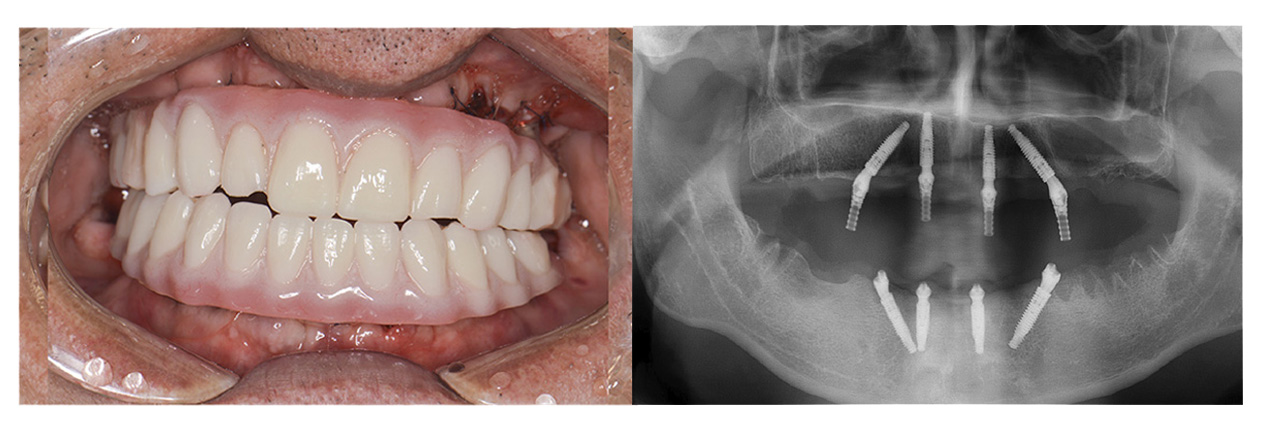

症例その2オールオン4 + ザイゴマ

• Before

• After

合わない総入れ歯と歯周病がひどい部分を全部除去してオールオン4とザイゴマにて治療した症例。